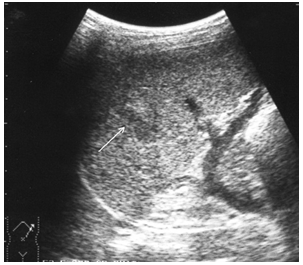

Чрескапсульные разрывы селезенки манифестируют нарушением непрерывности контура органа и визуализацией внутриорганных линий разрыва (рис. 7). Последние представляют собой гипоэхогенную или эхонегативную, в зависимости от времени, прошедшего после травмы, зону линейной или «ветвистой» формы с неровными и нечеткими контурами. Важно отметить, что прямые эхографические признаки, будучи патогномоничными для данного вида повреждений, не имеют облигатный характер. В частности, нарушение непрерывности контура селезенки наблюдается только у 25,4 % больных, а линия внутриорганного разрыва визуализируется в 60,3 % случаев. При этом возможность выявления указанных признаков в ранние сроки весьма проблематична и становится реальной только через 16–24 часа после травмы.

Рис. 7. Эхограмма чрескапсульного разрыва селезенки. Нарушение непрерывности контура указано стрелкой.

В связи с вышеизложенным особое клиническое значение приобретают косвенные эхографические признаки чрескапсульного разрыва органа, прежде всего внутрибрюшинного кровотечения, отмеченного у всех больных с таким характером травмы. Периспленическая гематома (рис. 8) представляет собой околоорганное скопление крови, полностью либо частично окружающее поврежденную селезенку и ограниченное такими анатомическими образованиями, как купол диафрагмы, задний листок париетальной брюшины, петли кишечника, фиксированные пряди большого сальника и т. д.

Рис. 8. Эхограмма чрескапсульного разрыва селезенки. Периспленическая гематома указана стрелками.

Следующим по значимости и частоте выявления косвенным эхографическим признаком чрескапсульного разрыва селезенки стала визуализация ткани большого сальника, фиксированного в зоне повреждения или окутывающего весь орган (рис. 9).

Рис. 9. Эхограмма чрескапсульного разрыва селезенки. Фиксированная прядь большого сальника указана стрелками.

Фрагментация (отрыв полюса) селезенки представляет, по сути, частный вариант чрескапсульного разрыва с полным разобщением фрагментов органа. Наряду с раздельной визуализацией фрагментов выявляются линии разрывов и вышеописанные косвенные признаки, характерные для данного вида повреждений (рис. 10).

Рис. 10. Эхограмма полного поперечного разрыва селезенки. Линия разрыва указана стрелками.